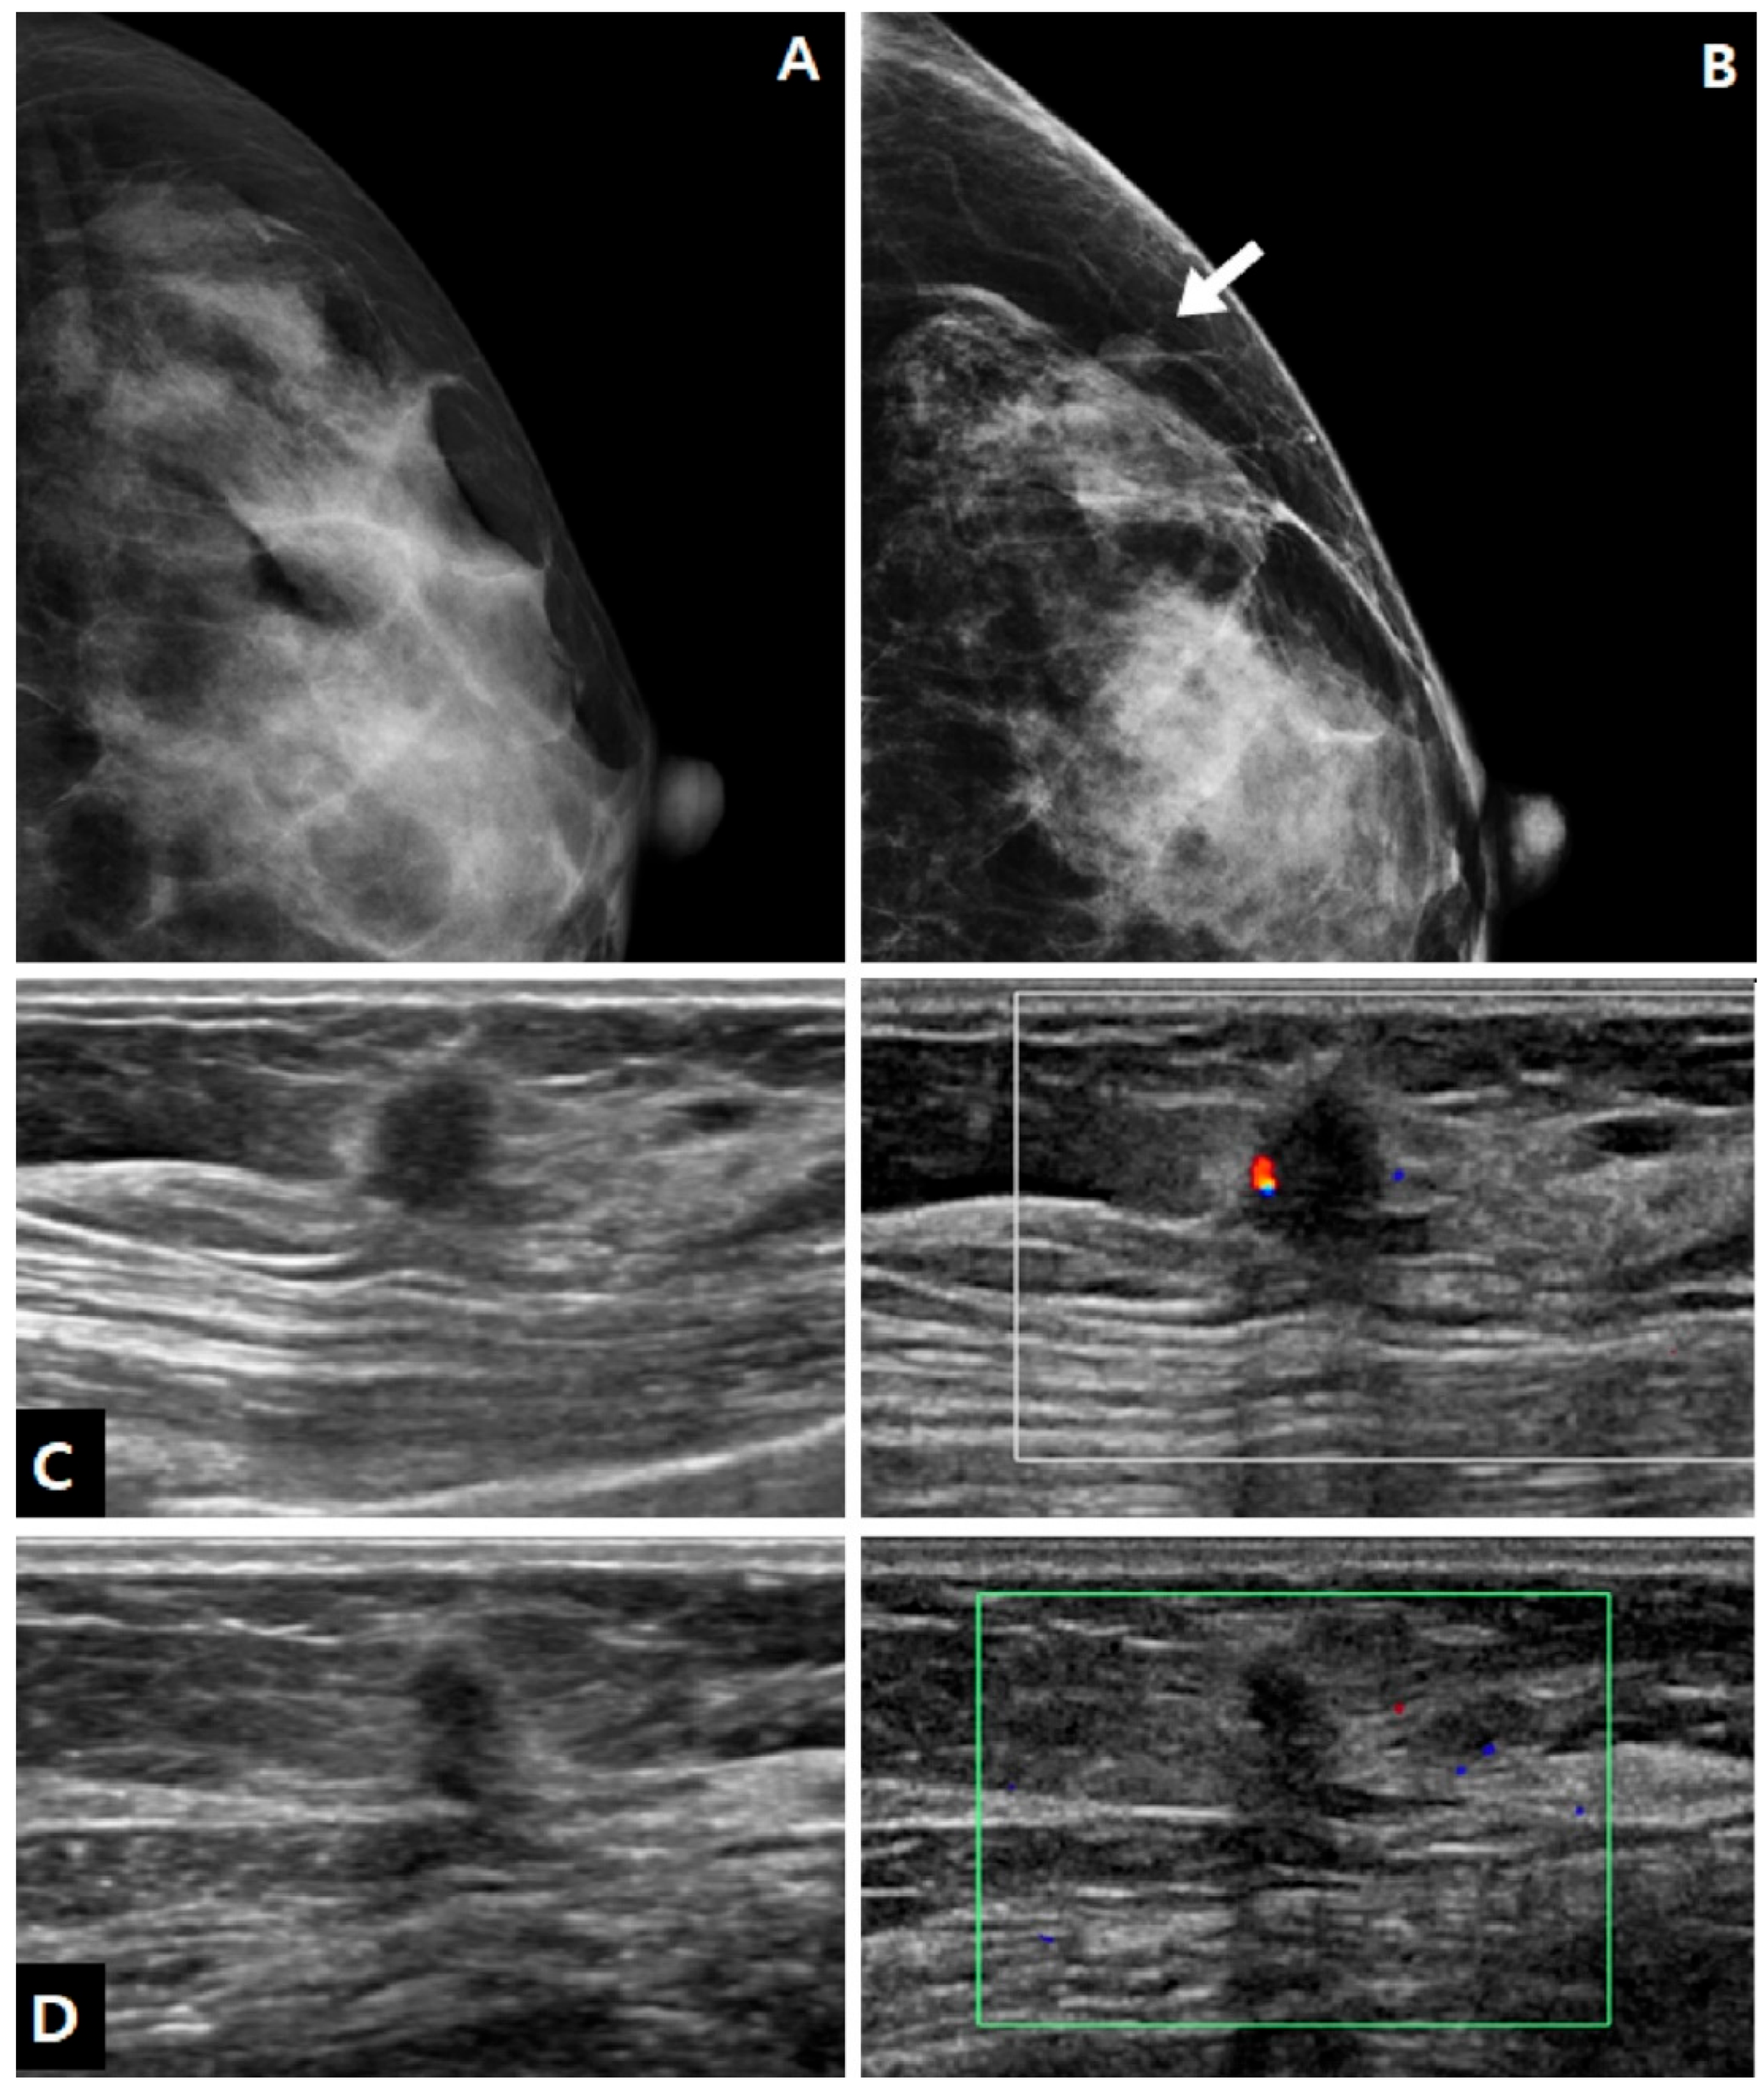

| Mass | 18/18 (100.0%) |

| Non-mass lesion | 0/18 (0.0%) |

| Size (cm, median) | 0.8 (0.6, 1.1) |

| Shape | |

| Round or oval | 9/18 (50.0%) |

| Tubular | 1/18 (5.6%) |

| Irregular | 8/18 (44.4%) |

| Margin | |

| Circumscribed | 8/18 (44.4%) |

| Not circumscribed | 10/18 (55.6%) |

| Echogenicity | |

| Hypoechoic | 3/18 (16.7%) |

| Isoechoic | 8/18 (44.4%) |

| Hyperechoic | 7/18 (38.9%) |

| Echogenic halo | 5/18 (27.8%) |

| Taller-than-wide | 11/18 (61.1%) |

| Posterior acoustic shadowing | 3/18 (16.7%) |

| Hypervascularity | 4/18 (22.2%) |

| Location | |

| Skin~subcutaneous layer | 3/17 (17.6%) |

| Subcutaneous layer | 2/17 (11.8%) |

| Subcutaneous layer~breast parenchyma | 9/17 (52.9%) |

| Breast parenchyma | 3/17 (17.6%) |

| BI-RADS category | |

| 3 | 7/18 (38.9%) |

| 4A | 9/18 (50.0%) |

| 4B | 1/18 (5.6%) |

| 4C | 1/18 (5.6%) |